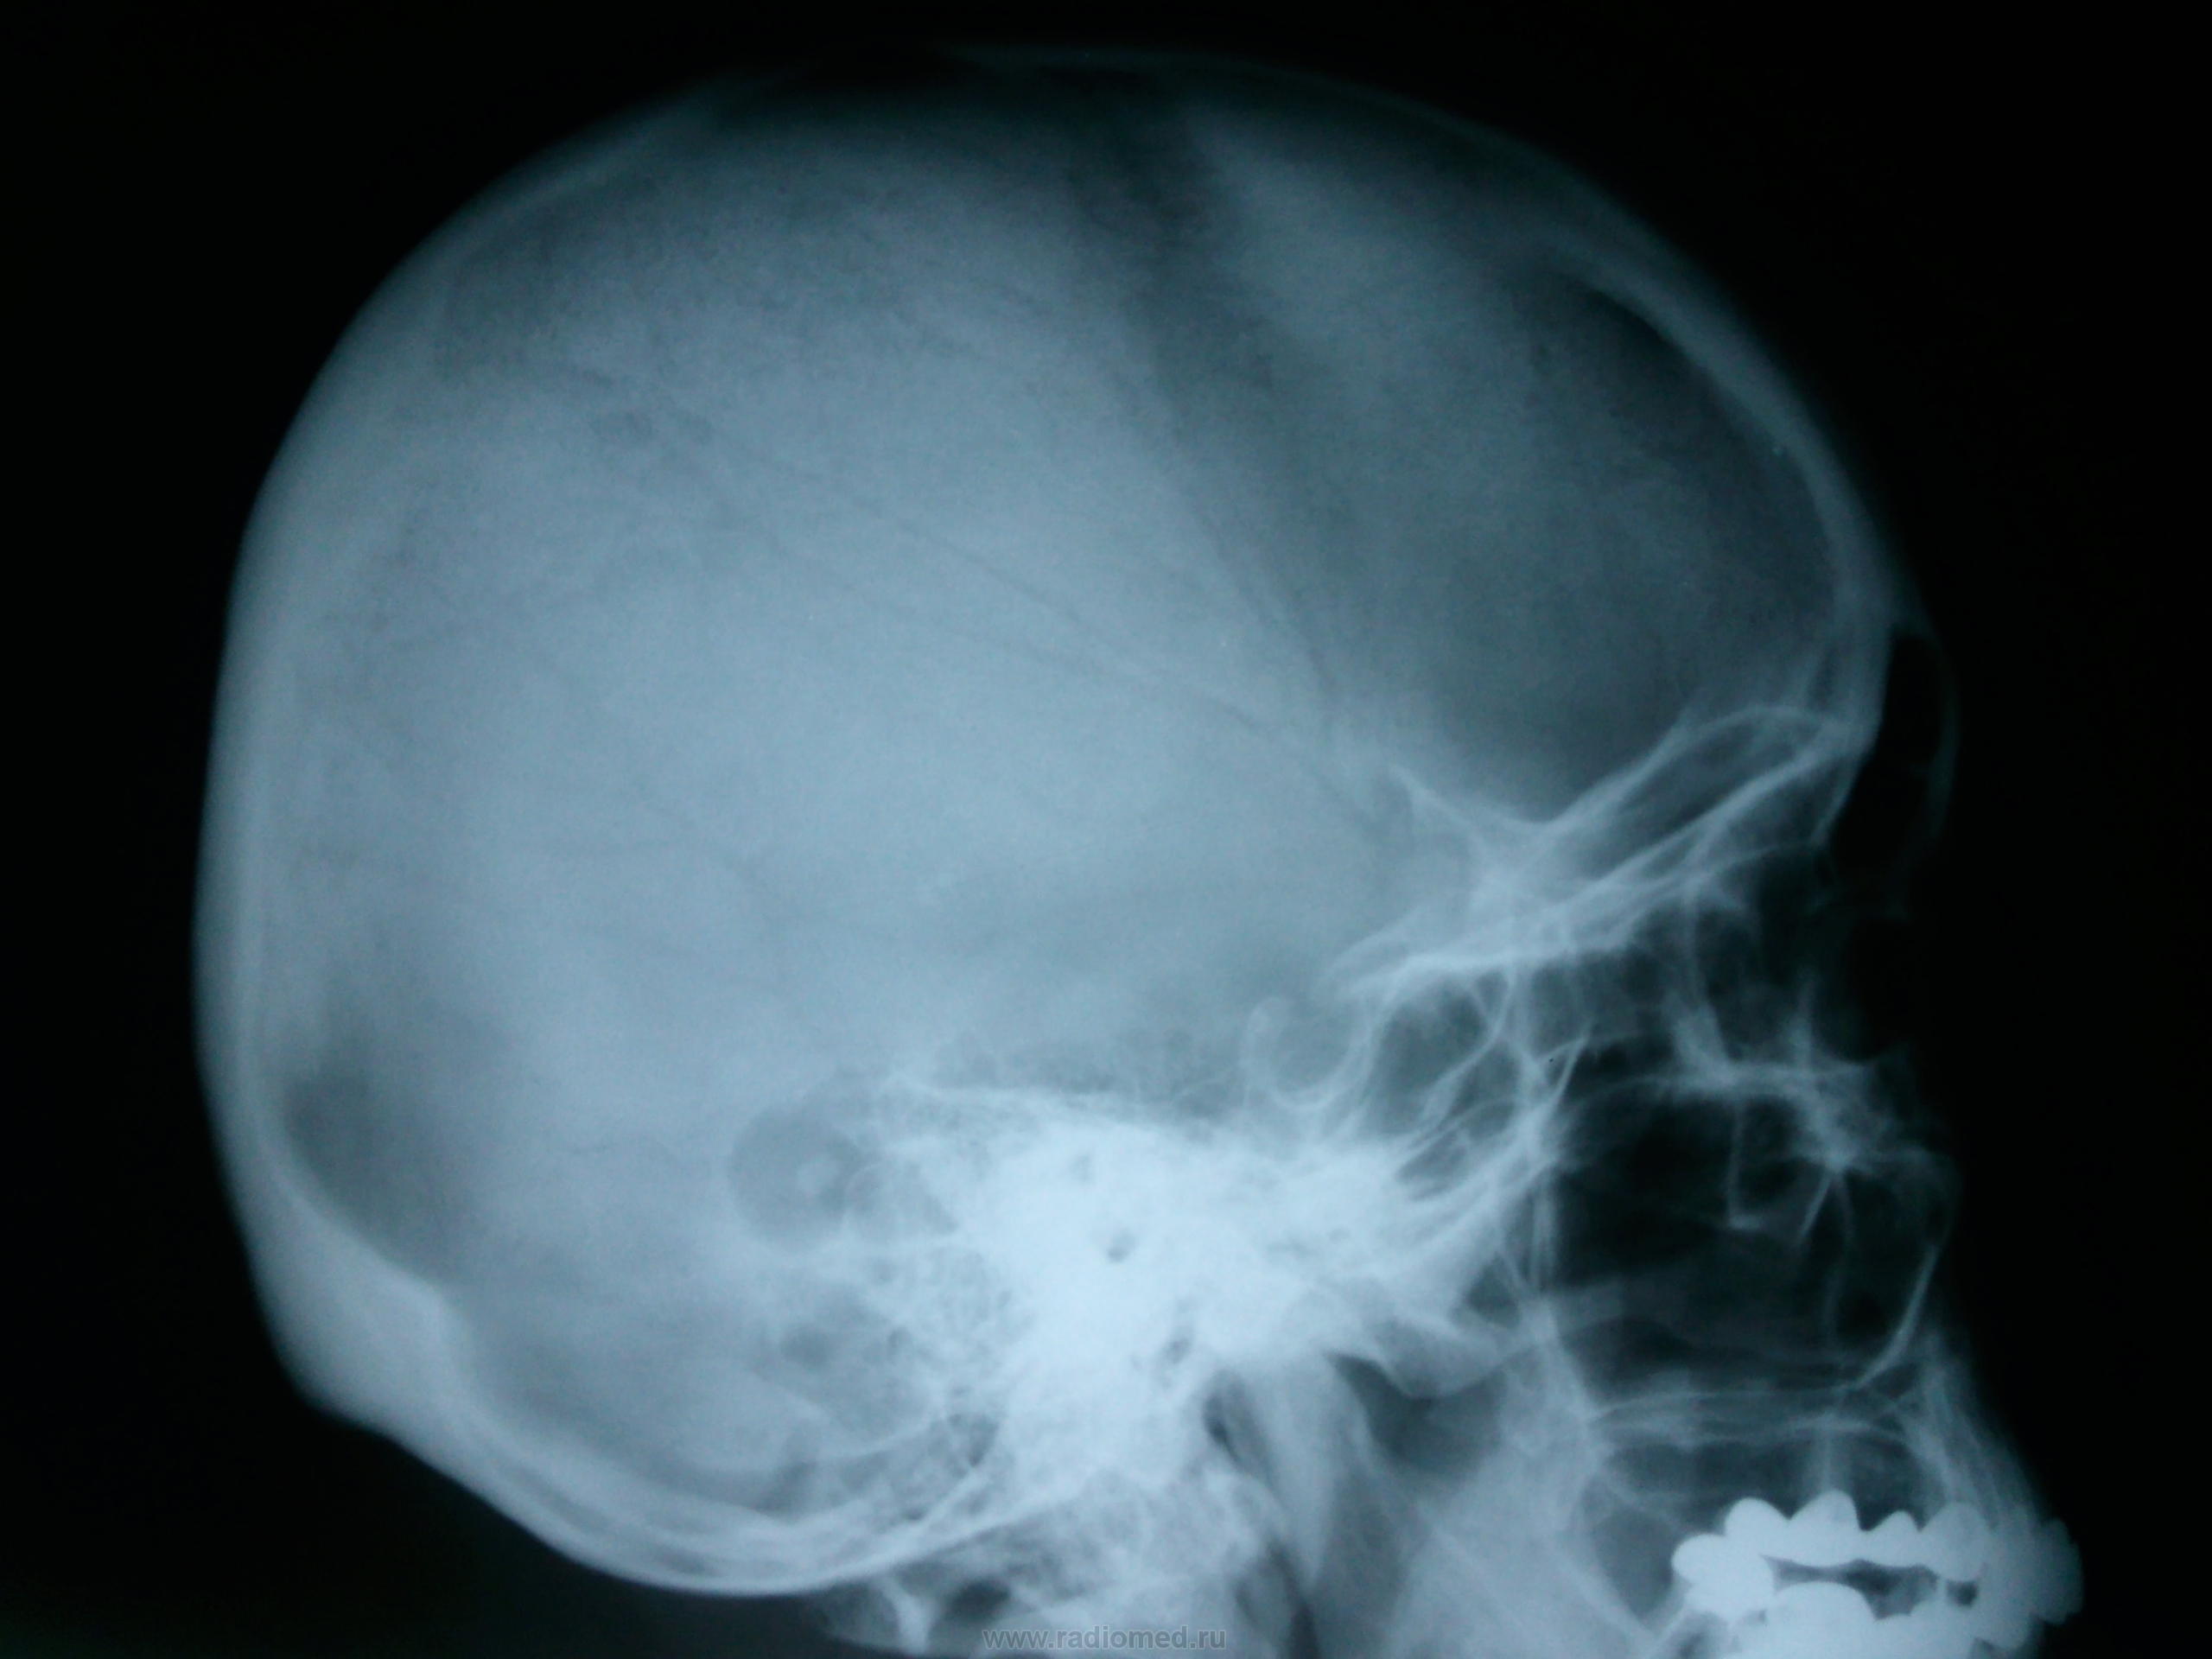

Пол пациента: Женский пол Тип патологии: Инфекция Область исследования: Череп и головной мозг Методы исследования: Rg Что это может быть? https://radiomed.ru/sites/default/files/styles/case_slider_image/public/user/134/foto0002.jpg?itok=rj0nO1qa https://radiomed.ru/sites/default/files/styles/case_slider_image/public/user/134/foto0003_001.jpg?itok=SAI4mEq1 ID:27007 Втр, 12/03/2013 - 23:00 #1 алкс Не на сайте Был на сайте: 10 лет 1 месяц назад Зарегистрирован: 24.10.2012 - 22:55 Публикации: 2915 Какая-то эндоуральная барабашка, с пластикой иль нет, но повреждение сосцевидного отростка фрезой видно. Возможно после гнойного эпитимпанита. Втр, 12/03/2013 - 23:18 #2 И.Бондаренко Не на сайте Был на сайте: 2 дня 16 часов назад Зарегистрирован: 13.09.2011 - 22:55 Публикации: 9206 Может быть ячейка сосцевидного отростка такая? Не пробовали смотреть скопически или косые снимки? Ср, 13/03/2013 - 01:29 #3 Алексей Игореви... Не на сайте Был на сайте: 6 лет 11 месяцев назад Зарегистрирован: 08.08.2012 - 21:52 Публикации: 786 По очертаниям подходит по ячейку. Вот какое происхождение секвестра внутри нее? Возможно и дефект посттраматический. "Обучая других - учишься сам". Н.И.Пирогов Ср, 13/03/2013 - 05:31 #4 ЧЮГ Не на сайте Был на сайте: 3 месяцев 2 недели назад Зарегистрирован: 31.10.2012 - 15:10 Публикации: 414 Прямая р-гр. срезана - похоже с левой стороны такая же ячейка. Ср, 13/03/2013 - 17:23 #5 Пантелеймон Не на сайте Был на сайте: 7 лет 8 месяцев назад Зарегистрирован: 16.07.2010 - 14:58 Публикации: 63 Холестеатома. А анамнез, клиника? Ср, 13/03/2013 - 17:30 #6 Фил Не на сайте Был на сайте: 6 лет 10 месяцев назад Зарегистрирован: 13.09.2011 - 16:24 Публикации: 137 А жалобы - есть ? Для холестеатомы локализация и проекция не подходящая . Ср, 13/03/2013 - 23:58 #7 brainmodel Не на сайте Был на сайте: 3 месяцев 1 неделя назад Зарегистрирован: 18.03.2010 - 22:04 Публикации: 2881 Этот "глаз" расположен кзади от углов Чителли обеих височных костей, так что ни под холестеатому, ни под фрезевое ложе не подходит. Варианты: - предоставить нормальную прямую проекцию (для начала) - прямое показание для снимков по Шюллеру и Майеру - достать пациента и выяснить анамнез, можно и прощупать интересующие области Без первых двух условий гадать можно много... Verum plus uno esse non potest.

Какая-то эндоуральная барабашка, с пластикой иль нет, но повреждение сосцевидного отростка фрезой видно. Возможно после гнойного эпитимпанита.

Может быть ячейка сосцевидного отростка такая? Не пробовали смотреть скопически или косые снимки?

По очертаниям подходит по ячейку. Вот какое происхождение секвестра внутри нее? Возможно и дефект посттраматический.

Прямая р-гр. срезана - похоже с левой стороны такая же ячейка.

Холестеатома. А анамнез, клиника?

А жалобы - есть ? Для холестеатомы локализация и проекция не подходящая .

Этот "глаз" расположен кзади от углов Чителли обеих височных костей, так что ни под холестеатому, ни под фрезевое ложе не подходит. Варианты:

- предоставить нормальную прямую проекцию (для начала)

- прямое показание для снимков по Шюллеру и Майеру

- достать пациента и выяснить анамнез, можно и прощупать интересующие области

Без первых двух условий гадать можно много...